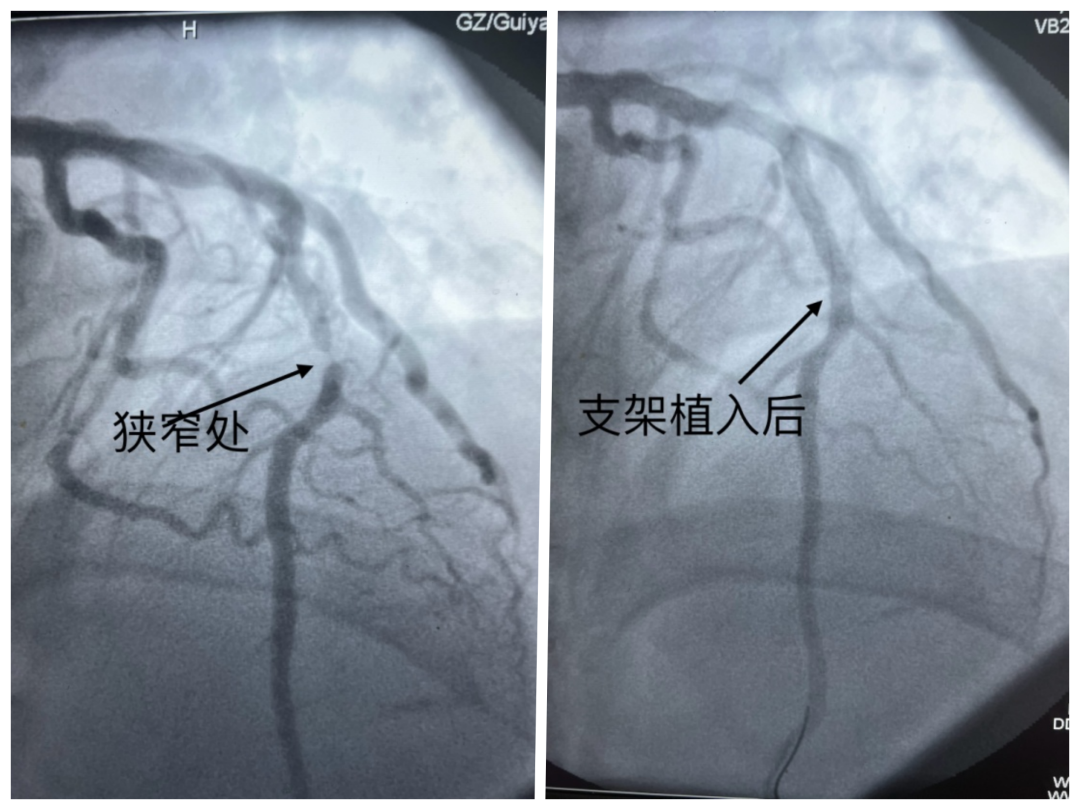

医生为其进行心电图检查,结果提示急性广泛前壁心肌梗死。随后,医生在其狭窄血管处植入支架,李先生转危为安。